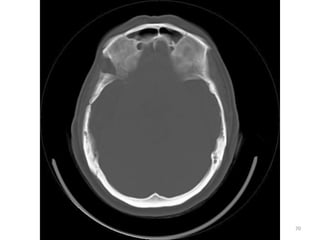

CORTES FOSSA POSTERIOR

81